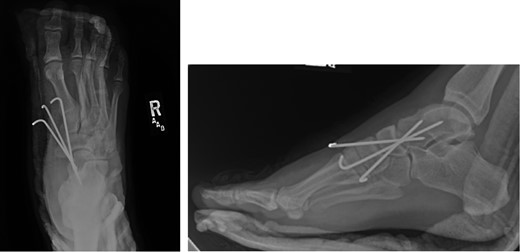

Once general anesthesia was induced, closed reduction was attempted using axial traction with the knee in flexion. Closed reduction was unsuccessful once again (Fig. 3) so the decision was made to attempt open reduction. An anteromedial approach was used dissect down to the talonavicular joint. Retractors were placed with care to avoid injury to tibialis anterior tendon or superficial peroneal nerve. The joint capsule was seen to be disrupted and further exposure revealed a thin, coronal fracture of the anteromedial aspect of the talar head measuring roughly 2 cm in length and 6 mm in thickness (Fig. 4). Once this fragment was removed, the subtalar and talonavicular joints were easily reduced. It was thought that this incarcerated fragment was the likely cause for the unsuccessful closed reduction. The talar head fragment was unamendable for stabilization due to its small size with poor healing potential, thus it was removed. The talonavicular joint was then percutaneously pinned in retrograde fashion with three K-wires (Fig. 5) to maintain anatomic reduction of the subtalar and talonavicular joints and the foot was splinted. At 2 weeks follow-up the patient was doing well and radiographs revealed no interval loss of reduction (Fig. 6).

Intraoperative AP view localizing the medial subtalar dislocation.